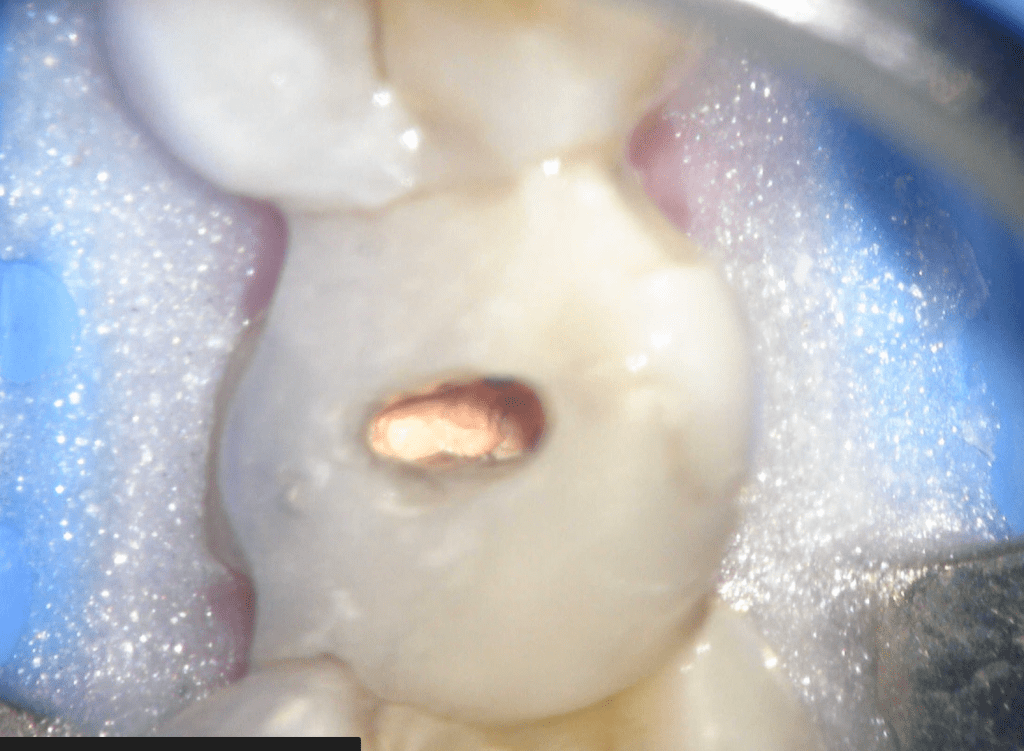

Reconstrucción preendodóntica

Molar superior

Reco preendo + 4 conductos molar superior

Reco preendo, 2o Molar superior